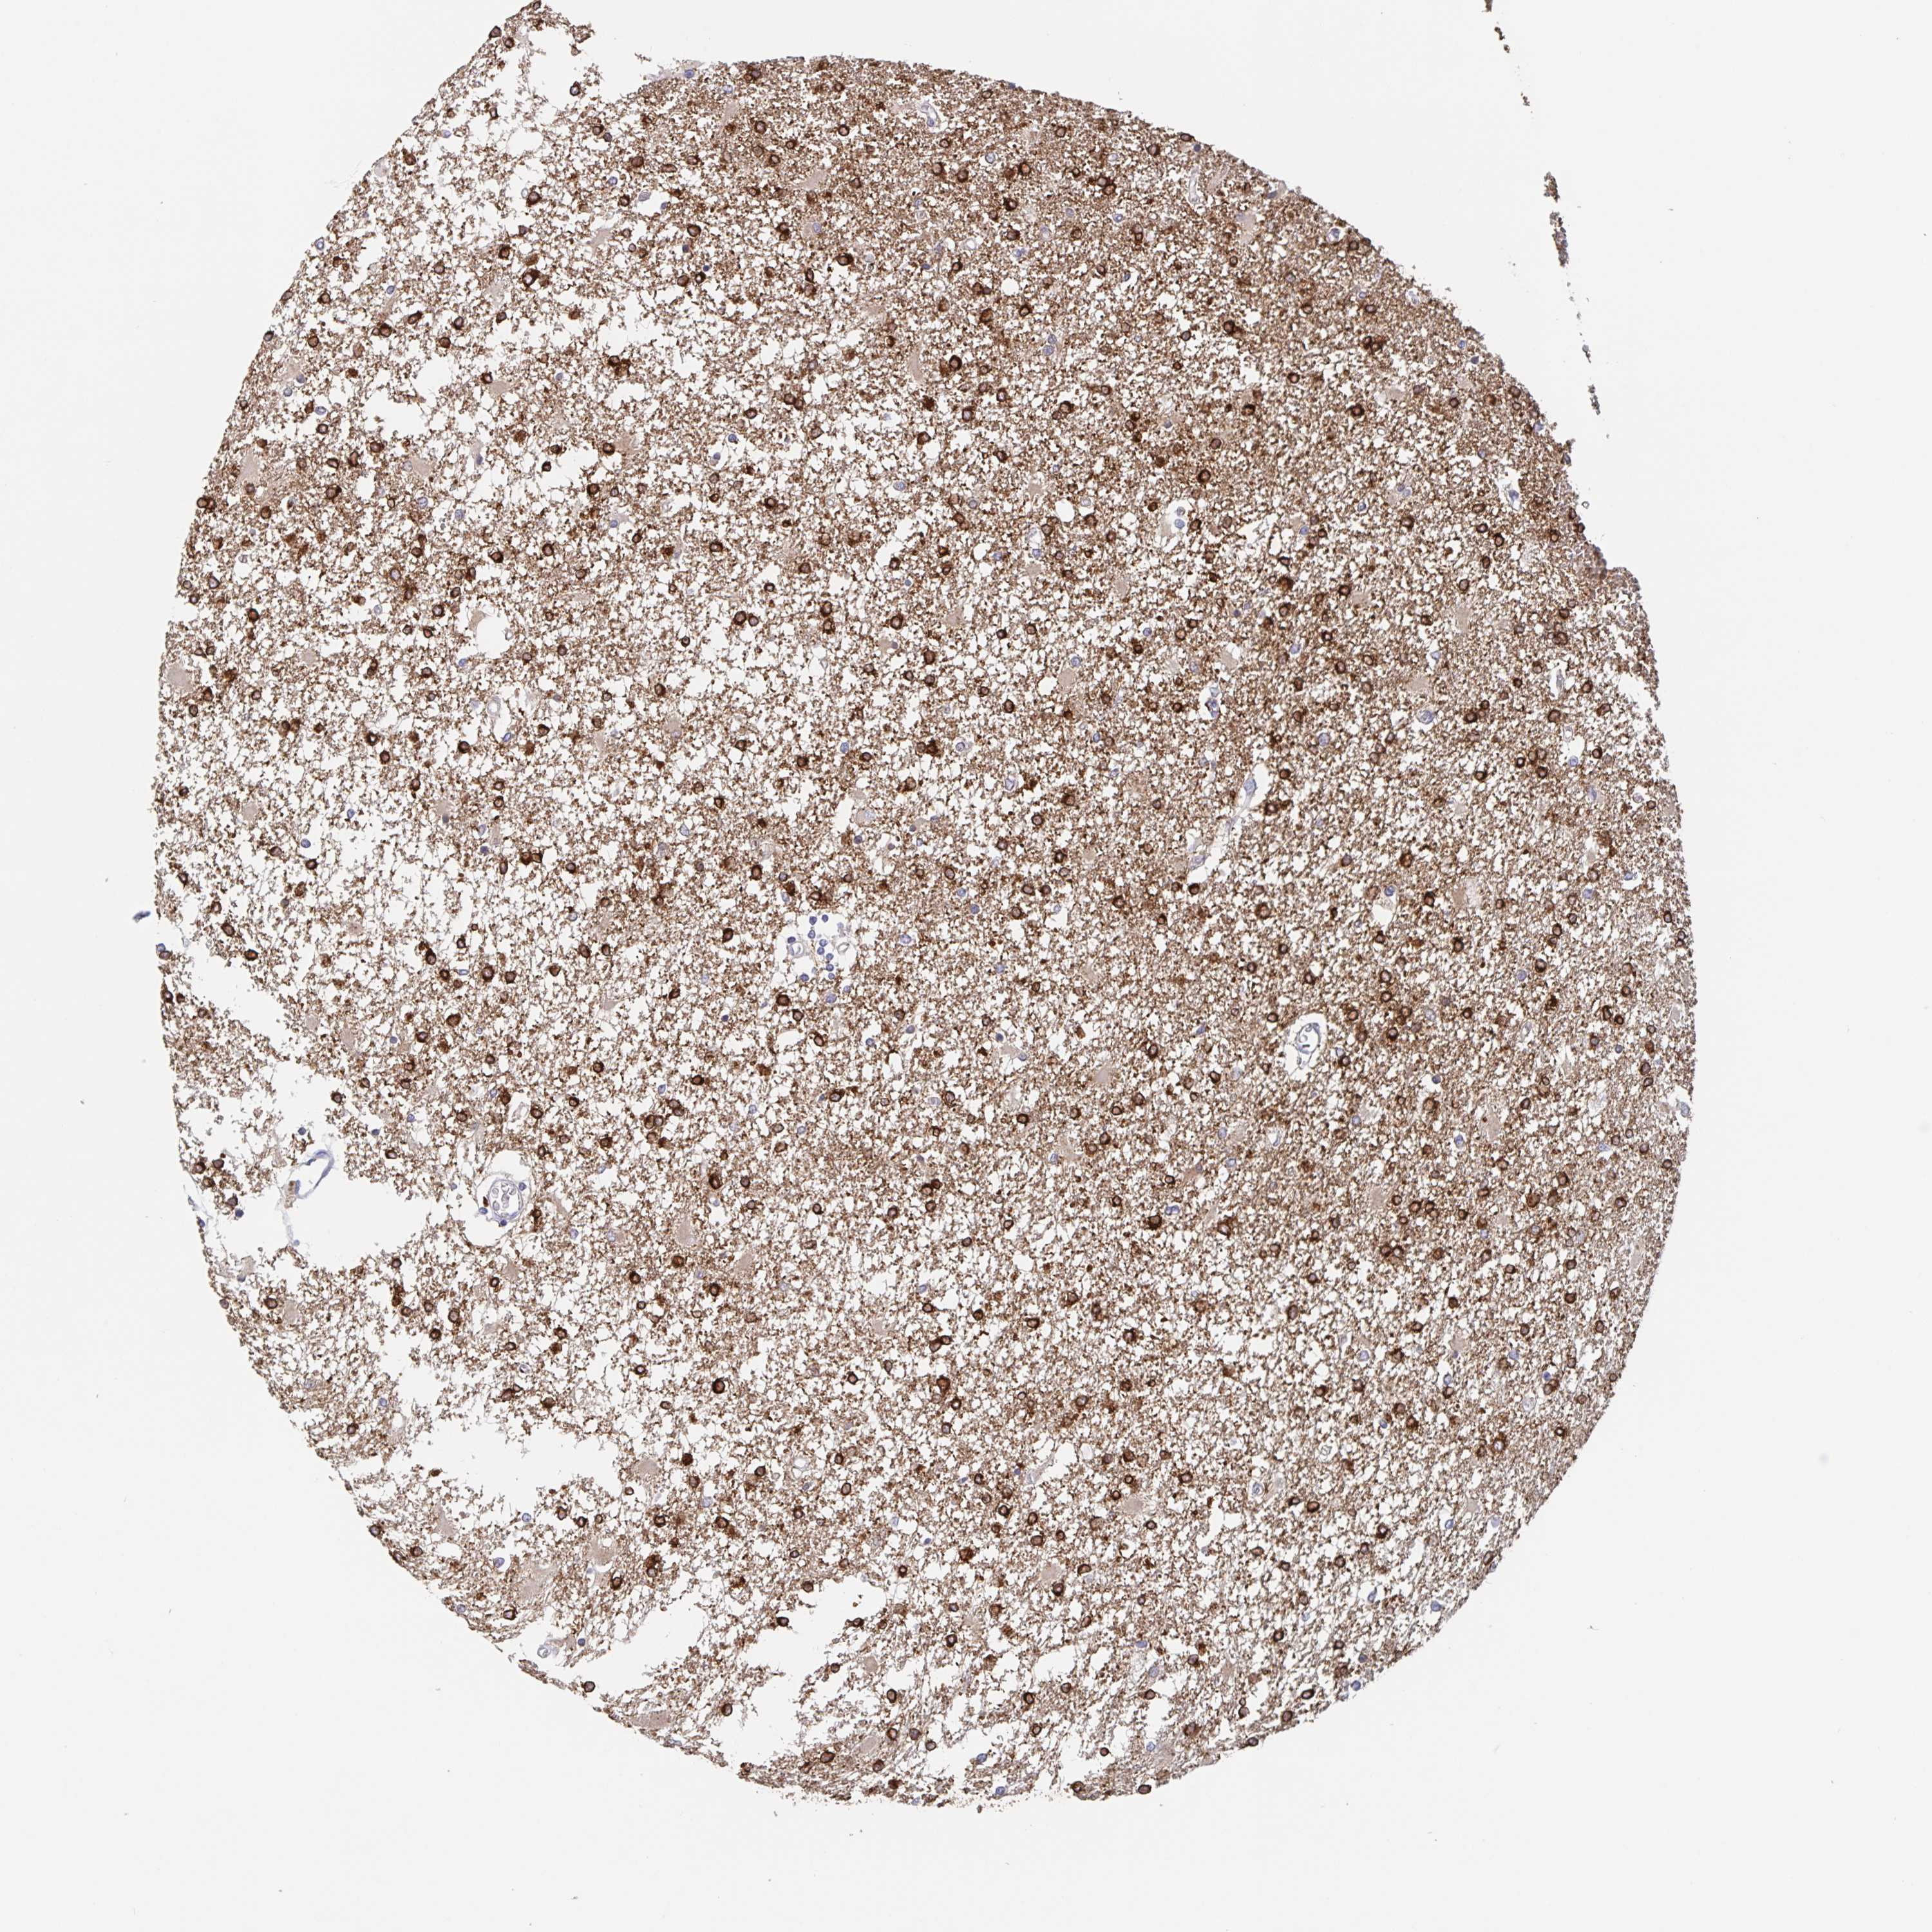

GLIOMA - Protein expressioni

A mouse-over function shows sample information and annotation data. Click on an image to view it in a full screen mode. Samples can be filtered based on level of antibody staining by selecting one or several of the following categories: high, medium, low and not detected. The assay and annotation is described here.

Note that samples used for immunohistochemistry by the Human Protein Atlas do not correspond to samples in the TCGA dataset.

Antibody stainingi

Antibody staining in the annotated cell types in the current human tissue is reported as not detected, low, medium, or high, based on conventional immunohistochemistry profiling in selected tissues. This score is based on the combination of the staining intensity and fraction of stained cells.

Each image is clickable and will lead to virtual microscopy that enables deeper exploration of all samples and also displays staining intensity scores, fraction scores and subcellular localization as well as patient and tissue information for each sample.

Antibody HPA027382

Antibody HPA061836

Staining

High

Medium

Low

Not detected

Intensity

Strong

Moderate

Weak

Negative

Quantity

>75%

75%-25%

<25%

None

Location

Nuclear

Cytoplasmic/membranous

Cytoplasmic/membranous,nuclear

Glioma, malignant, High grade

Glioma, malignant, Low grade